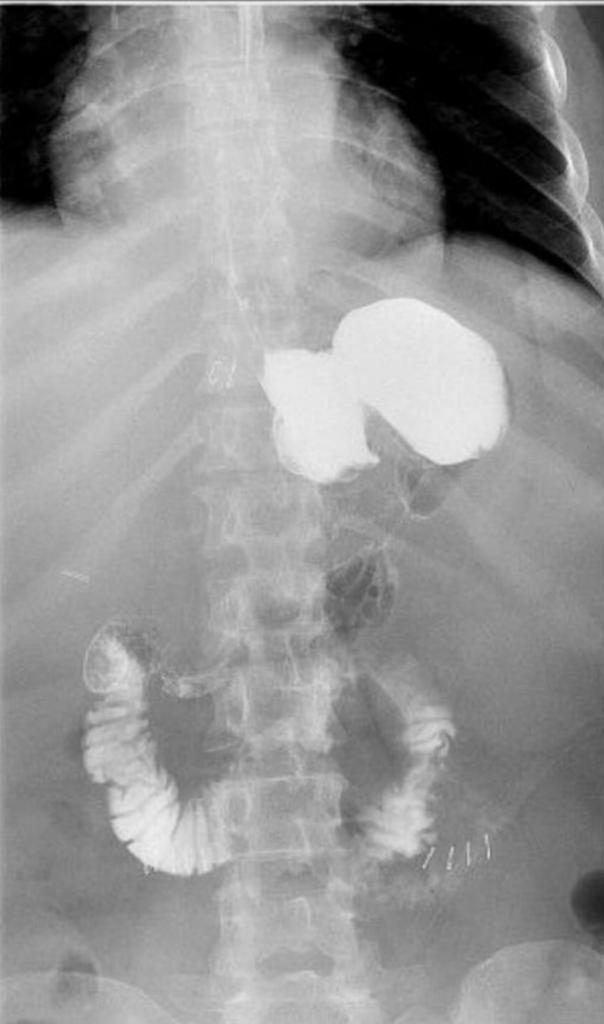

“بعد 11 شهراً من المعاناة” إجراء عملية ناجحةلمريضة خمسينية بمدينة سعود الطبية

أجرى فريق طبي مكون بعدداً من الكوادر الطبية المتخصصة في الجراحة العامة والباطنة والتخدير والتصوير الإشعاعي والطبقي ومساعديهم في تخصصات طبية أخرى في تخصص التمريض والعمليات بمدينة الملك سعود الطبية من إنهاء معاناة خمسينية استمرت

11 شهرًا تشكو من حالة سوء امتصاص شديد أدت إلى نقص حاد في الوزن من 124 كغ إلى 52 كغ حيث اجريت لها عملية تحويل مسار المعدة المصغر، وذلك من خلال إعادة الأمعاء الدقيقة إلى وضعها السابق بالإضافة لإعادة الاتصال للمعدة ، وتكللت ولله الحمد بالنجاح.